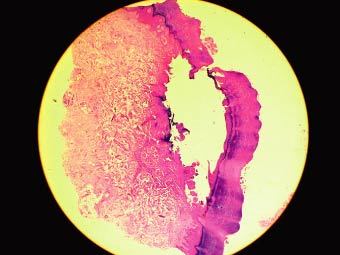

At autopsy, there were no obvious macroscopic pathological findings that could account for death. The main finding was non-specific acute pulmonary edema. The cause of death was left unascertained, pending further investigations. Histological examination of the heart, however, revealed a dense and florid inflammatory infiltrate comprising mainly lymphocytes within the myocardium. This was associated with necrosis of the myocardial fibres. The features were diagnostic of acute viral (lymphocytic) myocarditis (Fig. 13.3); histologically, the heart showed moderate and diffuse lymphocytic infiltration of the myocardium associated with myonecrolysis.

Fig. 13.3.

Case #1: Viral myocarditis with marked lymphocytic infiltrate within the myocardium, accompanied by necrosis of the myocardial fibres (H&E ×400)